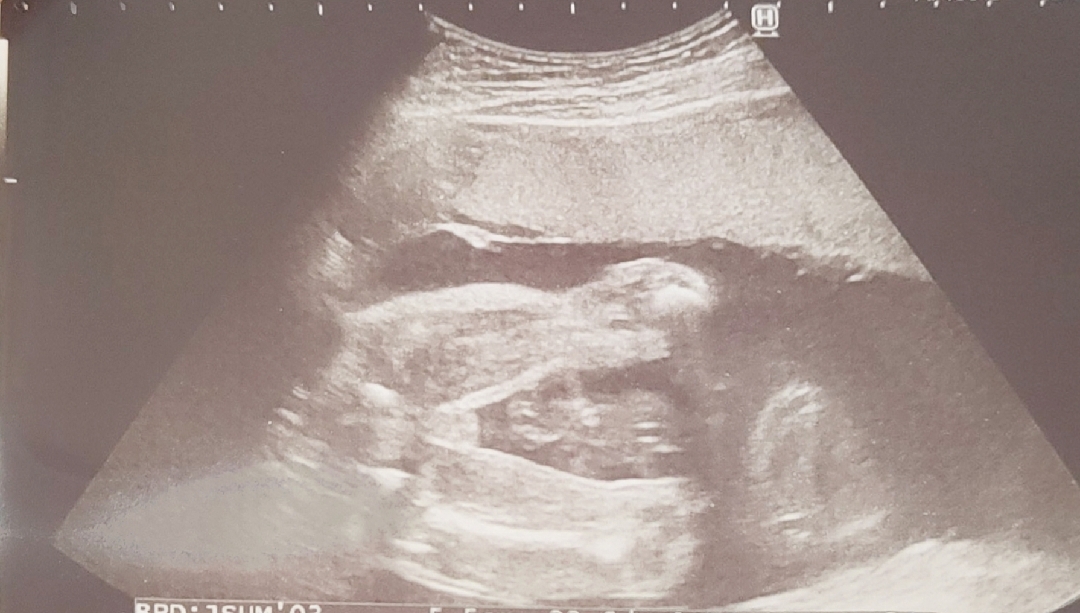

性別どっちだと思いますか?

皆さんは、女の子or男の子どっちに見えますか??

お股の写真ですかね?私は男の子に見えました!タマタマかな?あくまで予想です🤭 女の子でもワクワクですね😌🌸

お股の写真です。 見にくいですよね💦 どっちでも楽しみです♪